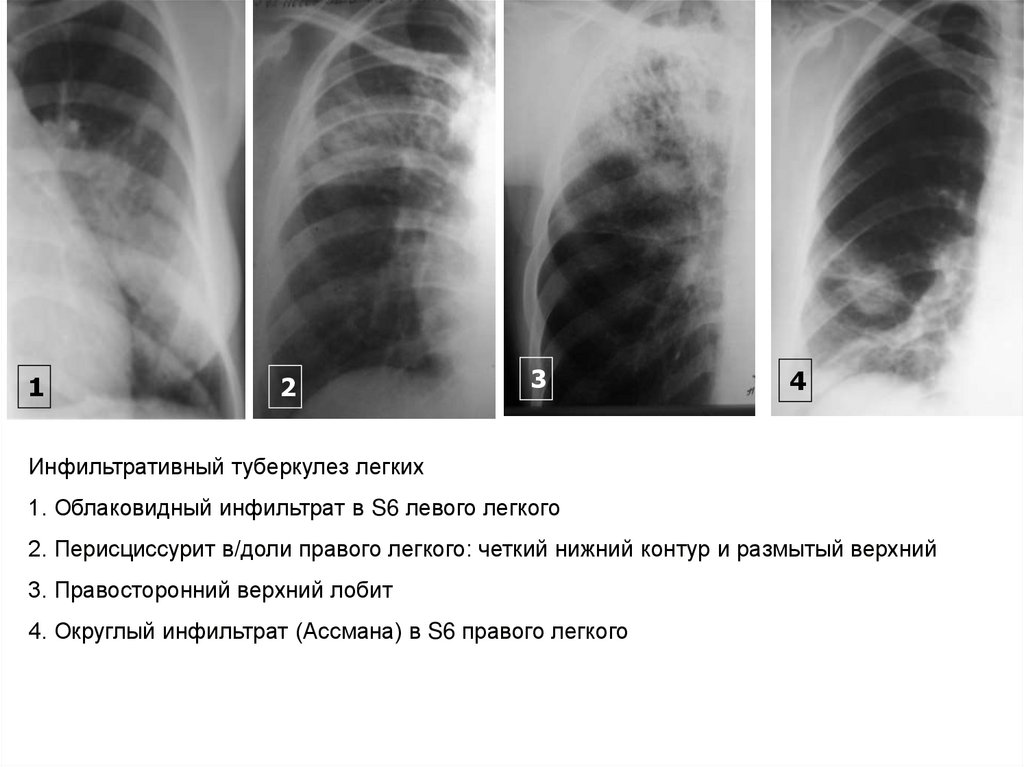

Иллюстрации по теме очагового и инфильтративного туберкулеза

Раздел: Фотодневник открытий